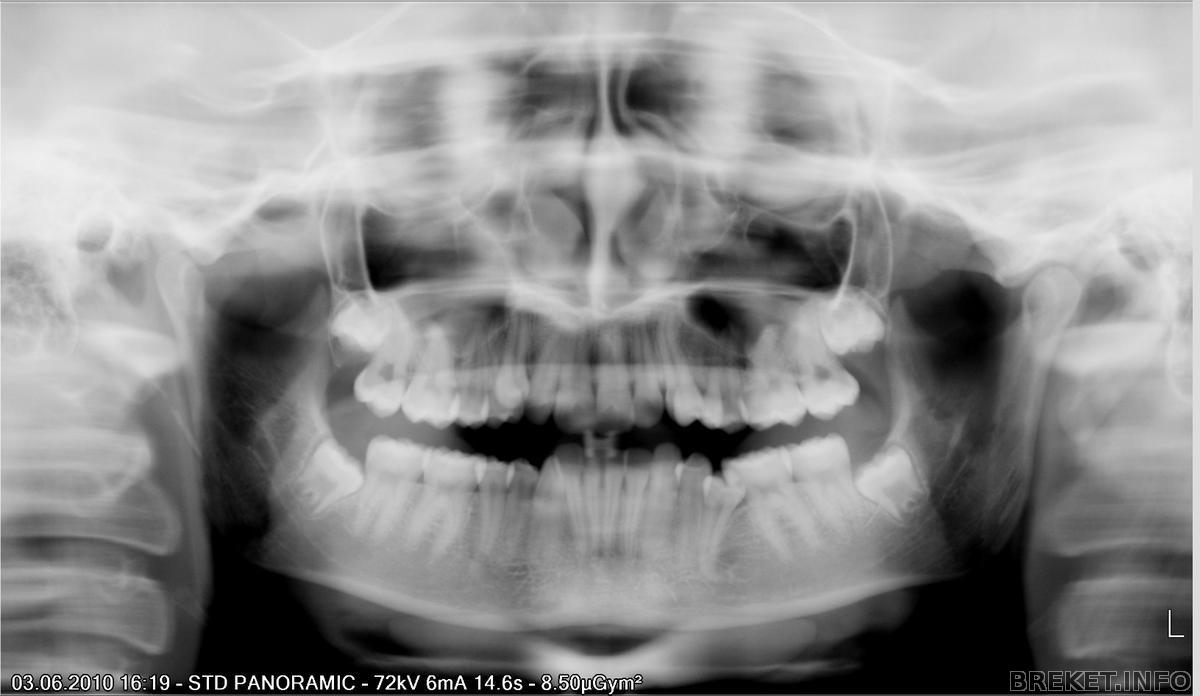

Вот ситуация пару лет назад (в принципе положение не изменилось), разве что удалили 8-ки